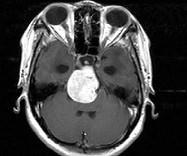

问题 女,32岁,头痛、右侧肢体功能障碍约1年,声间嘶哑,饮水呛咳,请根据所提供图像,选择最可能的诊断()

选项 A.(斜坡)脑膜瘤 B.(斜坡)脊索瘤 C.(斜坡)神经鞘瘤 D.(斜坡)软骨瘤 E.(斜坡)海绵状血管瘤

答案 C